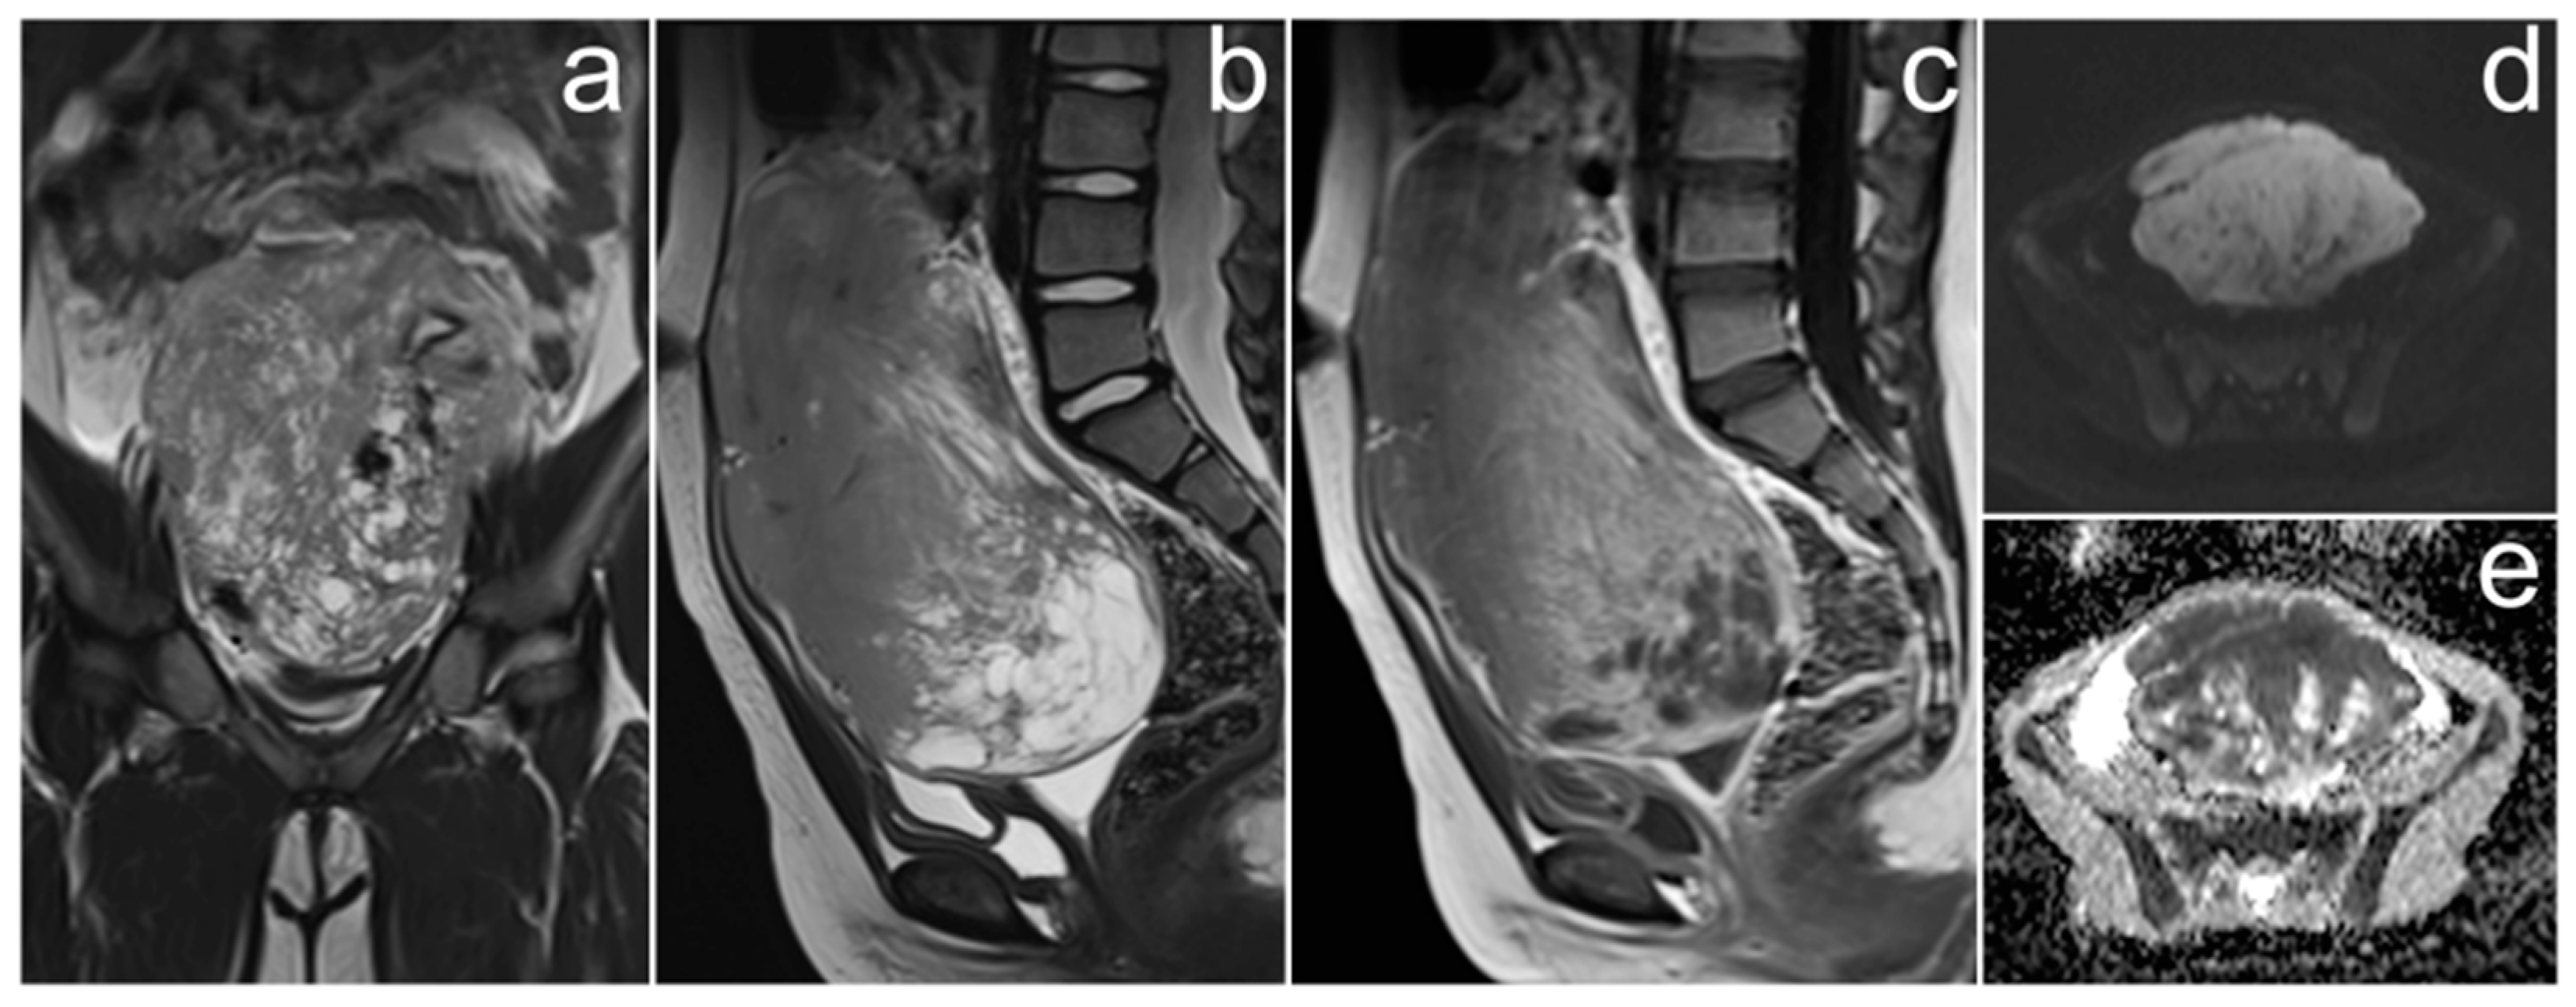

3.3. Diffuse Large B-Cell Lymphoma of the Ovaries

Case Report

3.4. Ovarian Sertoli–Leydig Cell Tumor with Rhabdomyosarcoma Due to DICER1 Syndrome

| Diffuse large B-cell lymphoma of the ovaries | bilateral, homogenous solid masses; “touching” large ovaries, small cysts arranged linearly around the periphery | elevated Ca-125 andLDH levels | non-specific; pain or discomfort in the abdominal cavity, enlarged abdominal circumference, irregular bleeding, B symptoms (fever, night sweats, or weight loss) |

| Ovarian Sertoli–Leydig cell tumor with rhabdomyosarcoma | variable; solid, solid-cystic, or exclusively cystic; T2 signal depends on amount of fibrous stroma; strong enhancement of solid elements in arterial phase | elevated testosterone level | virilization; associated with DICER1 syndrome |